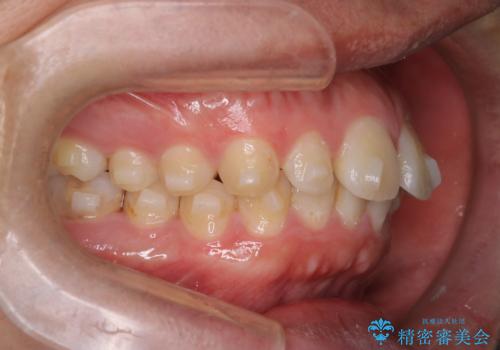

奥歯の噛み合わせもきちんと仕上げることができました。